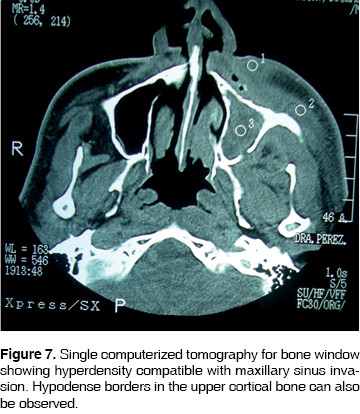

CASE 3

46 year old male with history of uncontrolled type II diabetes mellitus and uncontrolled, 15 year evolution. Systemic arterial hypertension. The patient's condition initiated 3 months prior to the visit; he informed of pain in the upper tooth, which he proceeded to extract himself. Two weeks after this event he experienced painful symptoms in the upper anterior region, informing of halitosis and foul taste in the mouth. He evolved for three months with peri-orbital edema, palpebral occlusion, skin fistula in the left nostril, 0.5 mm fistula intra-orally in the maxillary vestibule, with no egress of purulent matter. A computerized tomography was performed, where lytic areas were observed in the maxillary ascending process and maxillary process of malar bone, the maxillary sinus was invaded (Figure 7). CBC values were as follows: hemoglobin 11.3 g/dL, leukocytes 8.92 cpm, glucose 123 g/dL. Pharmacological treatment was undertaken with clindamycin 600 mg IV every 6 hours and Ceftriaxone, 1 g IV every 12 hours. At a later point, a subtotal hemimaxillectomy was performed preserving the lower orbital ridge. Surgery was performed under balanced inhalation general anesthesia, observing a 5 cm circum-vestibular approach, dissecting tissue until reaching bone exposition. Bone necrotic areas were observed. A 4.5 x 4 cm surgical specimen was harvested. Lesion free bone borders were clinically observed. Sutures were performed with treble cero polyglycolic acid material. The surgical sample was sent to the oral pathologist, who informed of maxillary chronic osteomyelitis with lesion free borders. The patient continued with the following out-patient pharmacological treatment: Procain G Penicillin, 800,000 IU every 12 hours for 30 days. Currently, after 8 months, the patient shows no relapse (Figure 8).